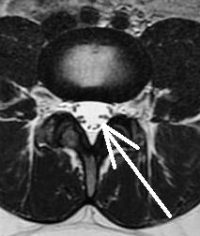

Disc herniation in an adolescent can occur in two ways, through a standard tear in the disc wall (a herniated disc) or through a fracture of the endplate of the vertebra. Just like in Scheuermann’s disease, the growth plate in the adolescent is still open. As stated before, the area of attachment of the growth plate to the vertebra is somewhat weak and a stress riser. The disc wall may not tear in its substance but may fracture off a piece of its insertion leaving a bony mass in the canal.

Interestingly, children and adolescents with disc herniations that compress nerves normally do not develop leg pain. This has to do with the resilience of the nerves in the adolescent. Pain is typically found in the back but can radiate down to the buttocks and possibly the upper thigh. Early diagnosis is helpful to return the child to sports and back pain exercises are usually recommended to help strengthen the muscles within the back and ease pain.